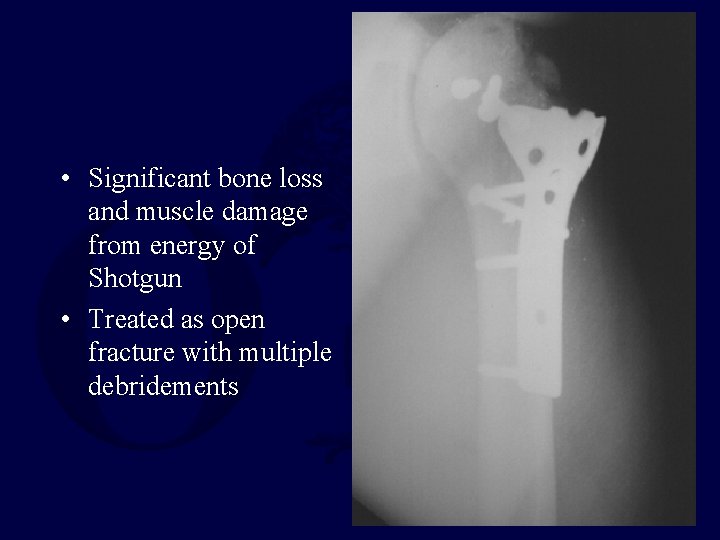

• 28 y. o. male • Shotgun load with large pellets • Neuro intact • Vascular intact • Large lateral wound from close range injury • Exploration – Wadding, packing and pellets, all removed • Repeat debridement at 72 hours

• Significant comminution not appreciated pre-op – Head split present • ORIF performed

• Significant bone loss and muscle damage from energy of Shotgun • Treated as open fracture with multiple debridements